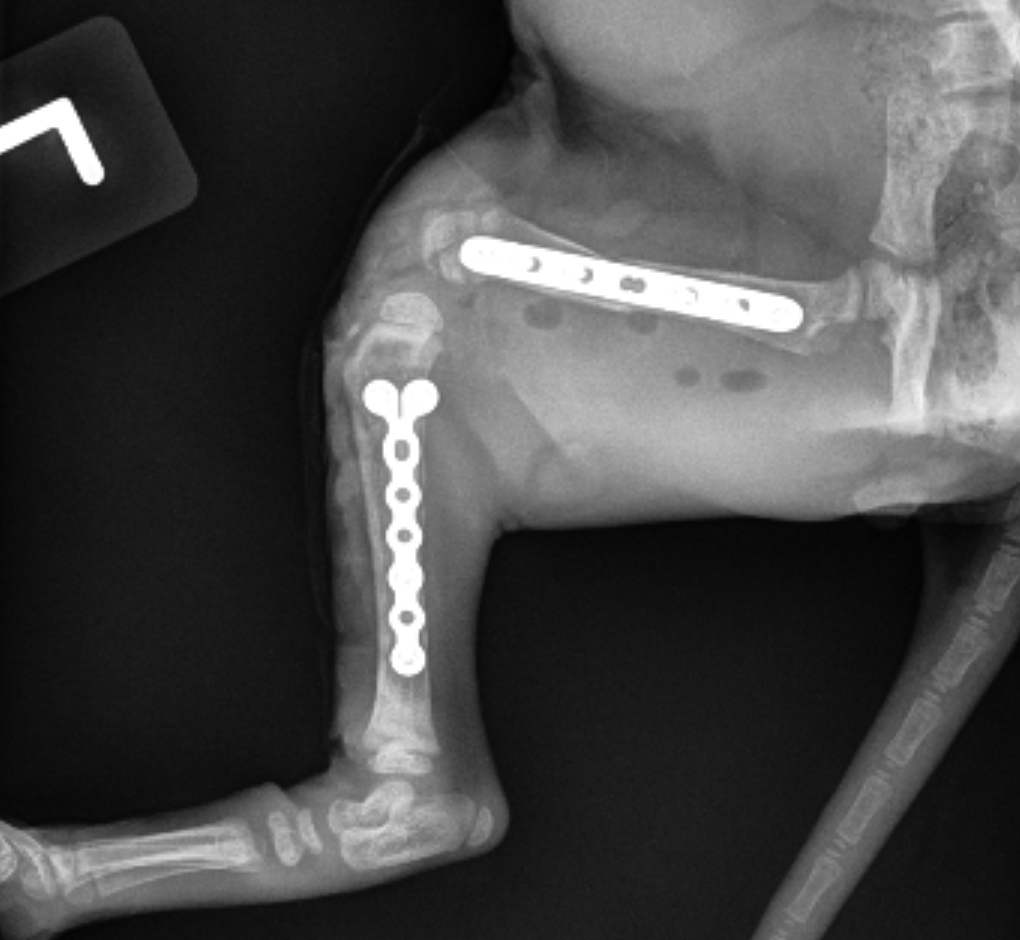

Fracture Repair

We provide surgical fracture repair for many types of broken bones. Treatment plans are individualized based on the location and complexity of the fracture, your pet’s age and size, and overall health.

Radius Fracture Before #1

Radius Fracture Before #2

Radius Fracture After